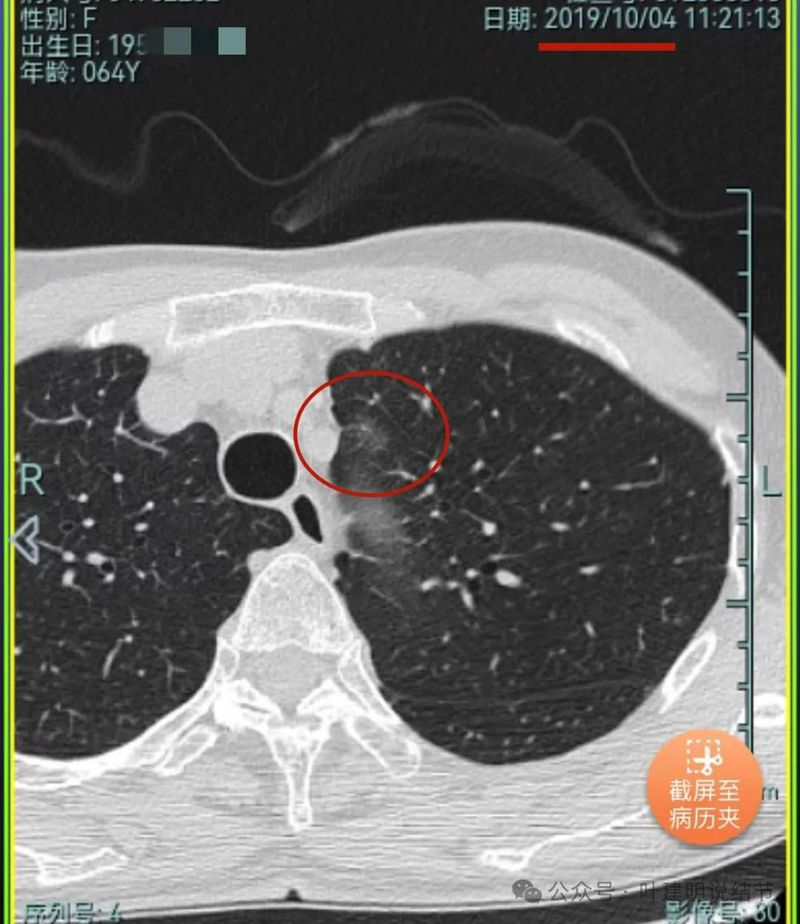

再看2021年随访的影像:

病灶1似乎中间高密度部分略有密度增高。

病灶2与2019年时相仿。

病灶3仍是混合密度,进展不显著。

病灶4仍是伴钙化的,也没有明显进展。

病灶5较前密度略显杂乱,整体密度应该有所增高。

病灶6轮廓较前清楚,灶内有血管穿行,也有轻微胸膜牵拉。

原病灶7已经被切除。